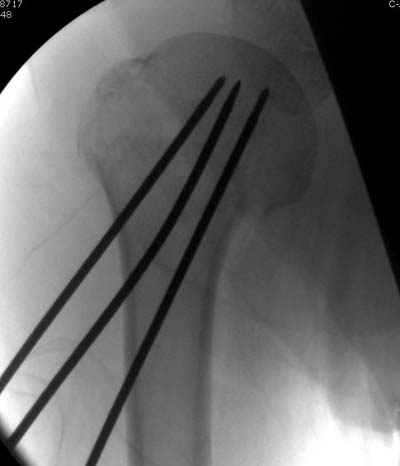

Сегодня взял больного повторно в операционную, не скажу, что повторная репозиция через неделю после первой попытки, была простая.

После удаления спиц попытался манипулировать отломками, но безуспешно, поэтому пришлось пользоваться периостальным элеватором, чтобы устранить смещение отломков и перепровести спицы. Проверил и перепроверил стабильность фиксации под ЭОПом, завтра Рг- будет готов, вот и поглядим....

Да. У нас довольно скромный опыт такого остеосинтеза (по 2 случая - плечо и наружная лодыжка), дошли до использования самого простецкого троакара, через который мы сверлим кость и вводим 6 мм стержни, когда накладываем аппарат. Соответственно, в качестве забойника отлично работает любой стержень от аппарата Илизарова. Еще из наших туземных особенностей - страшная любовь к спицевым дистракторам, поэтому делали в нем. Результат у этой дамы неизвестен, т.к. она из области и уехала рожать сразу после остеосинтеза, сейчас прошло больше 5 месяцев...

Что-то, наверно, сделали мы не совсем оптимально, поскольку у Анатолия Федровича и его соратников как-то красивее "раскрываются" спицы в головке плеча - надеюсь, он прокомментирует и подскажет, что надо подправить.